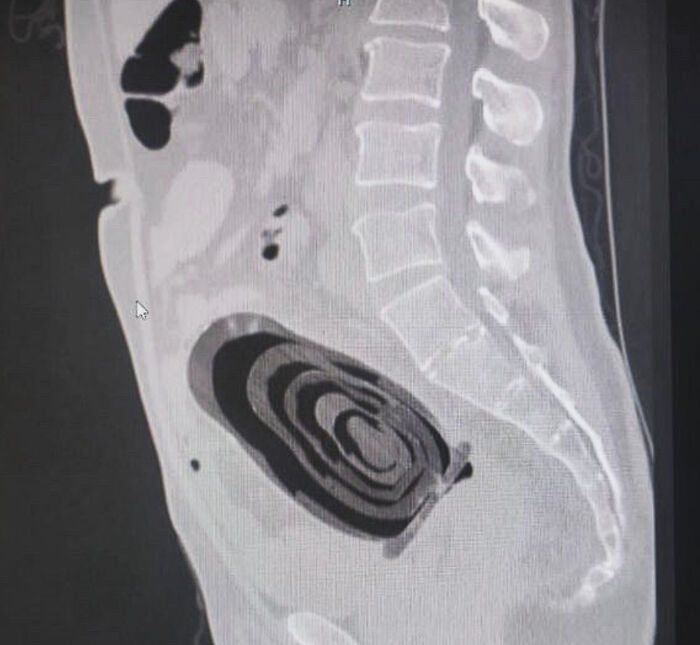

A 66-Year-Old Man “Accidentally” Fell On A Matryoshka Doll This Last Christmas Eve Night In Rome

it happens to the best of us you are cleaning the top of the curtains naked standing on stool you fall backwards and the doll just happens to be standing at bottom of the ladder can happen to anyone